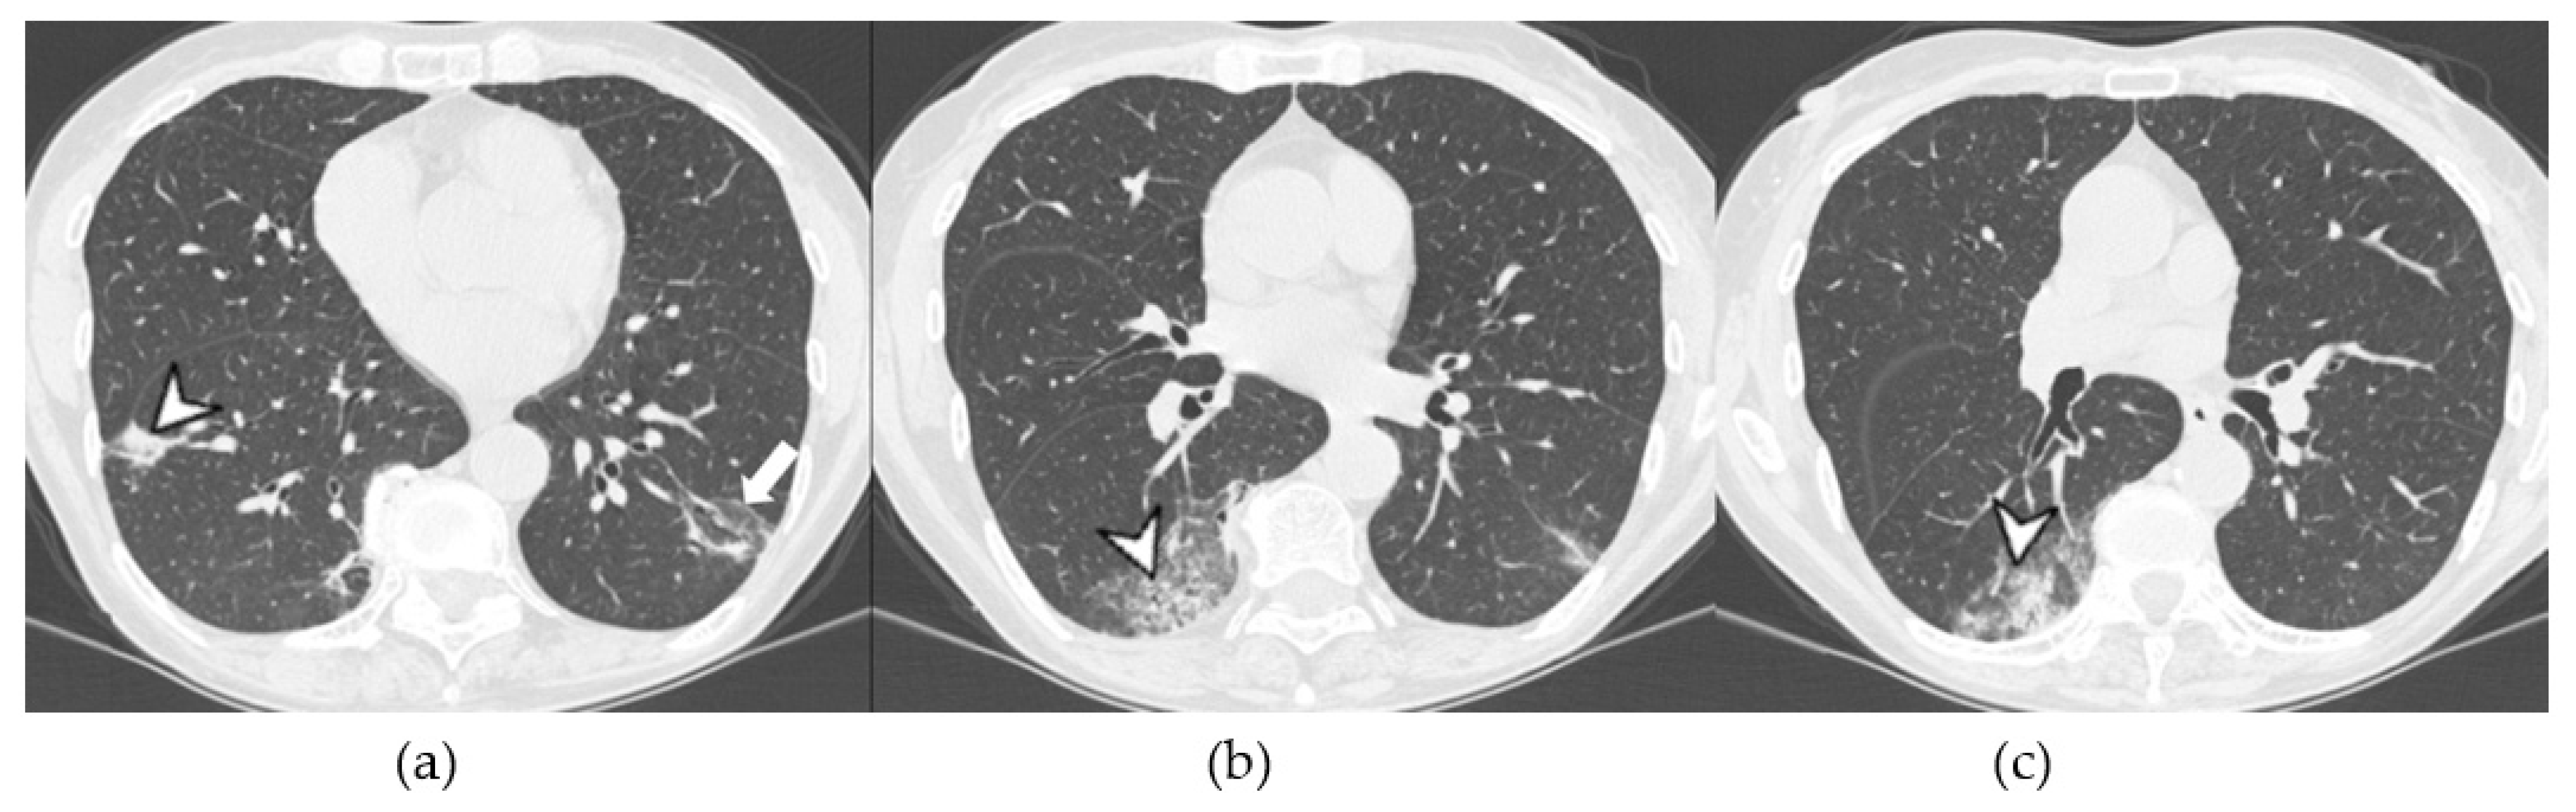

Acute Type

| Lesions | GGO, reticulations, consolidations | consolidations, GGOs | |

| Distribution | Homogeneous; lower lung lobes, along bronchovascular bundles and lung periphery; loss of volume of lower lobes | Patchy; peripheral lower lobes or along the bronchovascular bundles | |

| CT pattern | NSIP OP NSIP-OP UIP DAD-unclassifiable | 50% 20% 25% 10% +/− | 20% 50% 25% <5% ++ |